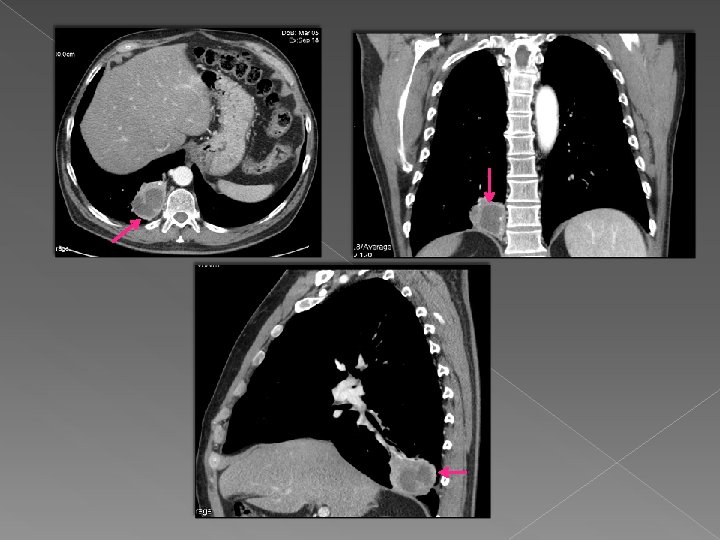

Caso 1 Paciente de 62 años en estudio por masa en LID y hemoptisis.

Caso 1 Paciente de 62 años en estudio por masa en LID y hemoptisis. Tras el reformateo multiplanar se visualiza en LID una masa con centro necrótico y áreas de abscesificación en su interior.